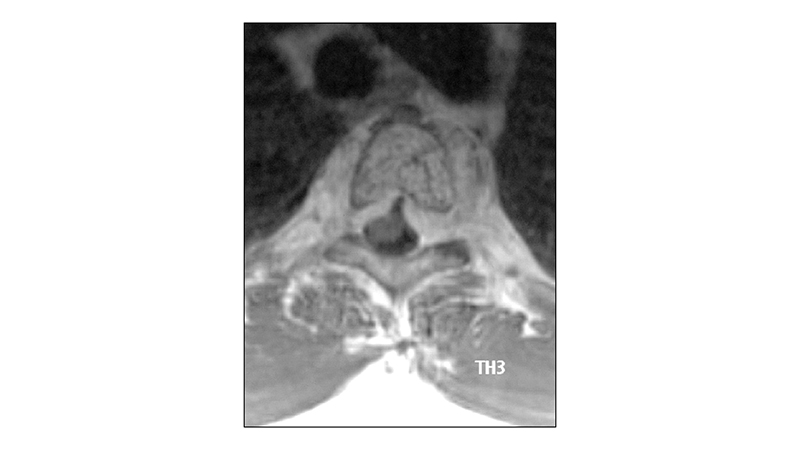

Εικόνα 8: Μαγνητική τομογραφία, με σκιαγραφικό, στο επίπεδο του Θ3, αμέσως μετά τον εμβολισμό: Το αιμαγγείωμα παρουσιάζει σημαντική συρρίκνωση της εξωσωματικής επεκτάσεως του. Η επέκταση προς τα πίσω ενδοκαναλικά έχει βελτιωθεί σημαντικά. Το ίδιο και πλάγια προς τα πλάγια σπονδυλικά τρήματα.

peristatiko aimaggeiwmatos spondulikhs sthlhs.008